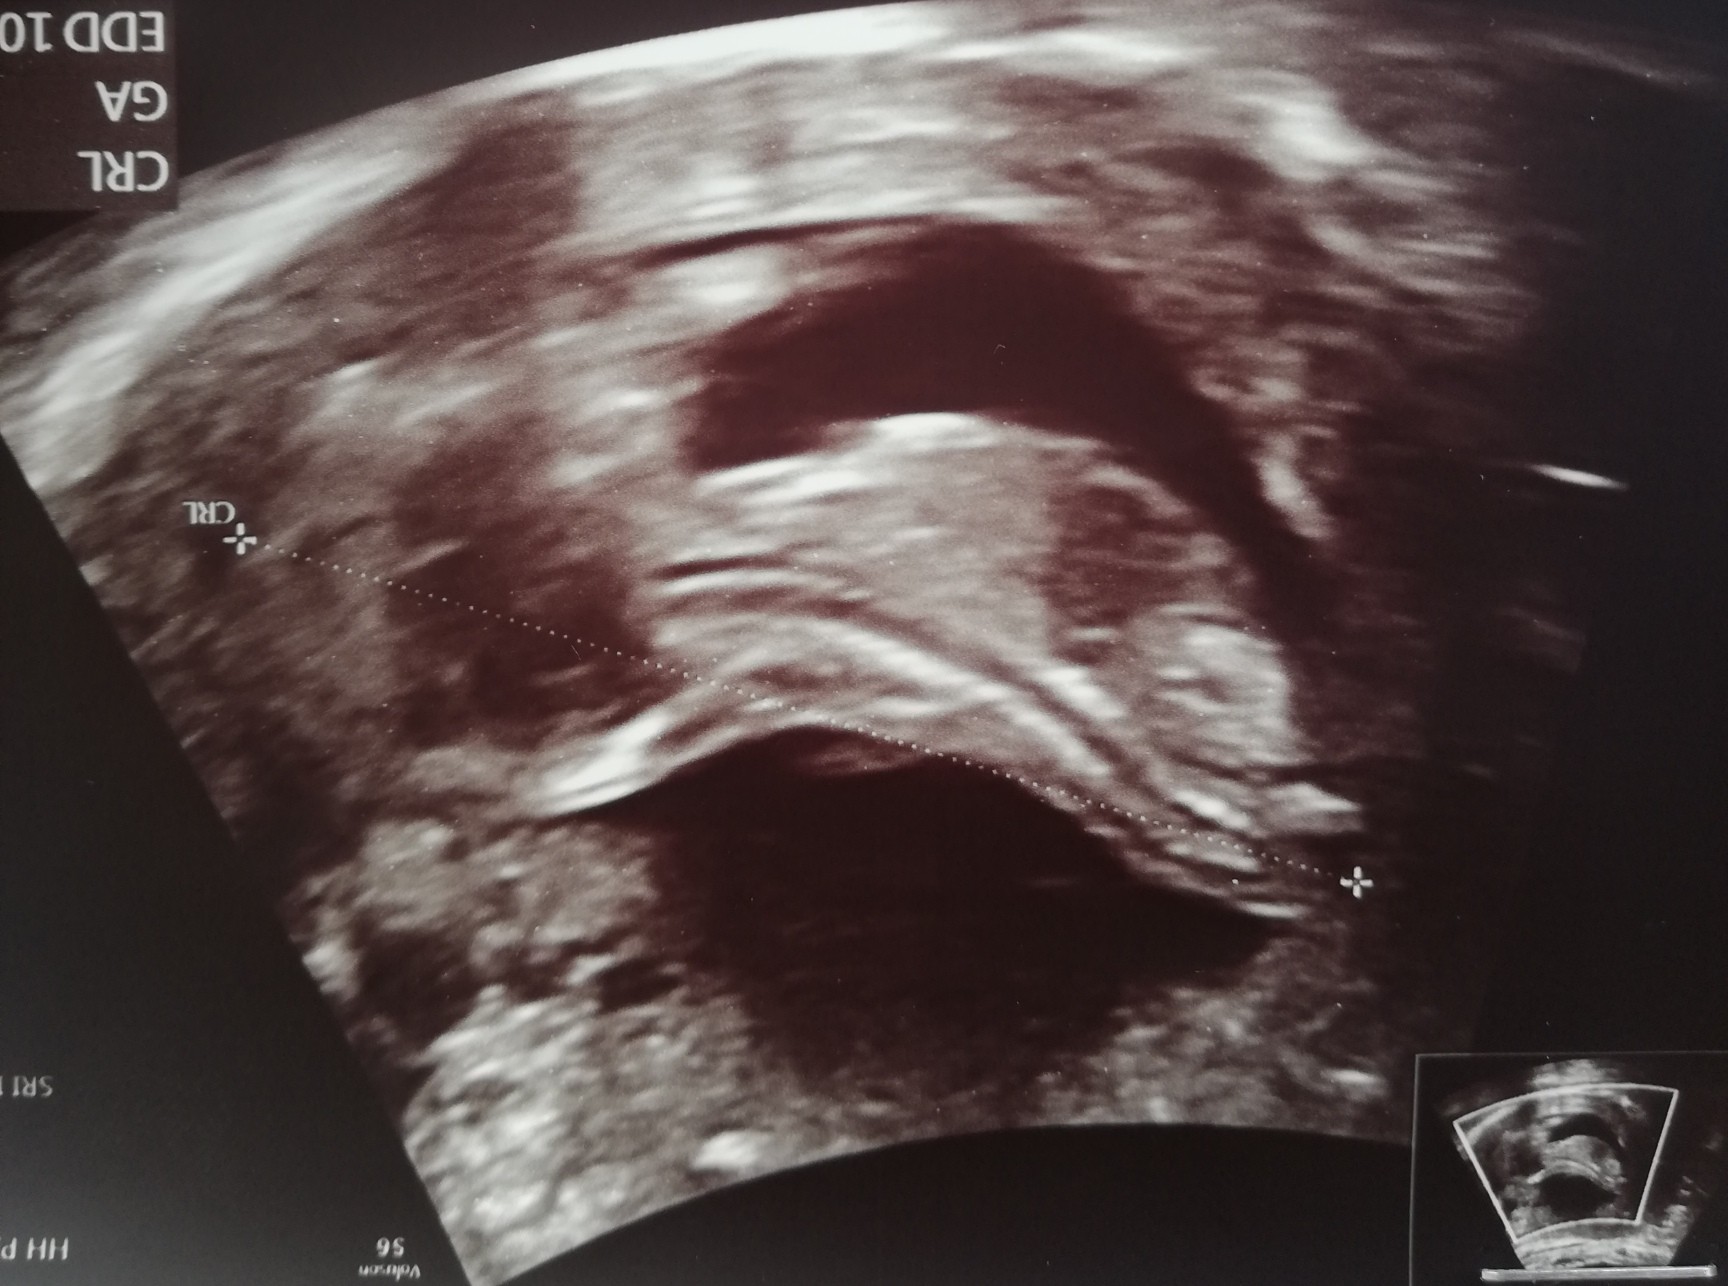

Ja wiem o które miejsce wczoraj Ci chodziło, bo sama tak myślalam. Ale to było za nisko, tak jakby przedłużenie kręgosłupa 😅 tutaj też mam wrażenie, że w sumie to może nie być nub bo też trochę nisko. Wyżej niż to wczoraj, ale nisko

• IMG_20200603_133458.jpg

IMG_20200603_133458.jpg

313,2 KB · Wyświetleń: 67

U mnie dzisiaj 13+5. Jak zaczęło się usg to dzidzia się nie ruszała i pani doktor mówi "no, ruszaj się" i tak mnie cisnęła w brzuch i młody zaczął się pięknie obracać[emoji16][emoji16] i mówi jaki grzeczny dzidziuś, posłuchał od razu :D

Wielkość na dziś to 8,2cm [emoji173]

Hej. Ja tylko na chwilke. Wiem ze niektore osoby pamietaly ze mam prenatalne i pewnie czekają na wieści. Duma mnie rozpiera i tryskam dzis pozytywna energia po badaniu wiec chce to pokazac calemu swiatu [emoji4] płeć nieznana bo sie nie pokazaliśmy [emoji28] straszny wiercioch ogólnie. Ryzyko takie jak na zdj [emoji4] 2 w tabelce to skorygowane. Cale 6.6 cm szczescia. Także u nas dobrze gdyby coś. Buziaki [emoji173]

Dziewczyny u nas wszystko okej [emoji176] wszystkiej parametry dobre, serduszko bije 163/min. Dzidzia ma 6,72cm, ryzyko wad niskie. No i jestem szczęśliwa, bo najprawdopodobniej będzie córcia [emoji7] ewidentnie było widać widełki [emoji179]